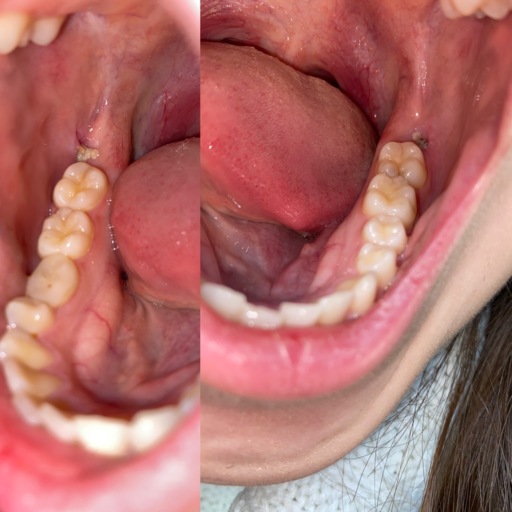

Is the a dry socket or normal healing?

got pulled 3 days ago curious whether or not it’s a dry socket isn’t into much pain I would really appreciate if someone would answer. feels normal just wondering has stitches around it. not to deep of a hole.